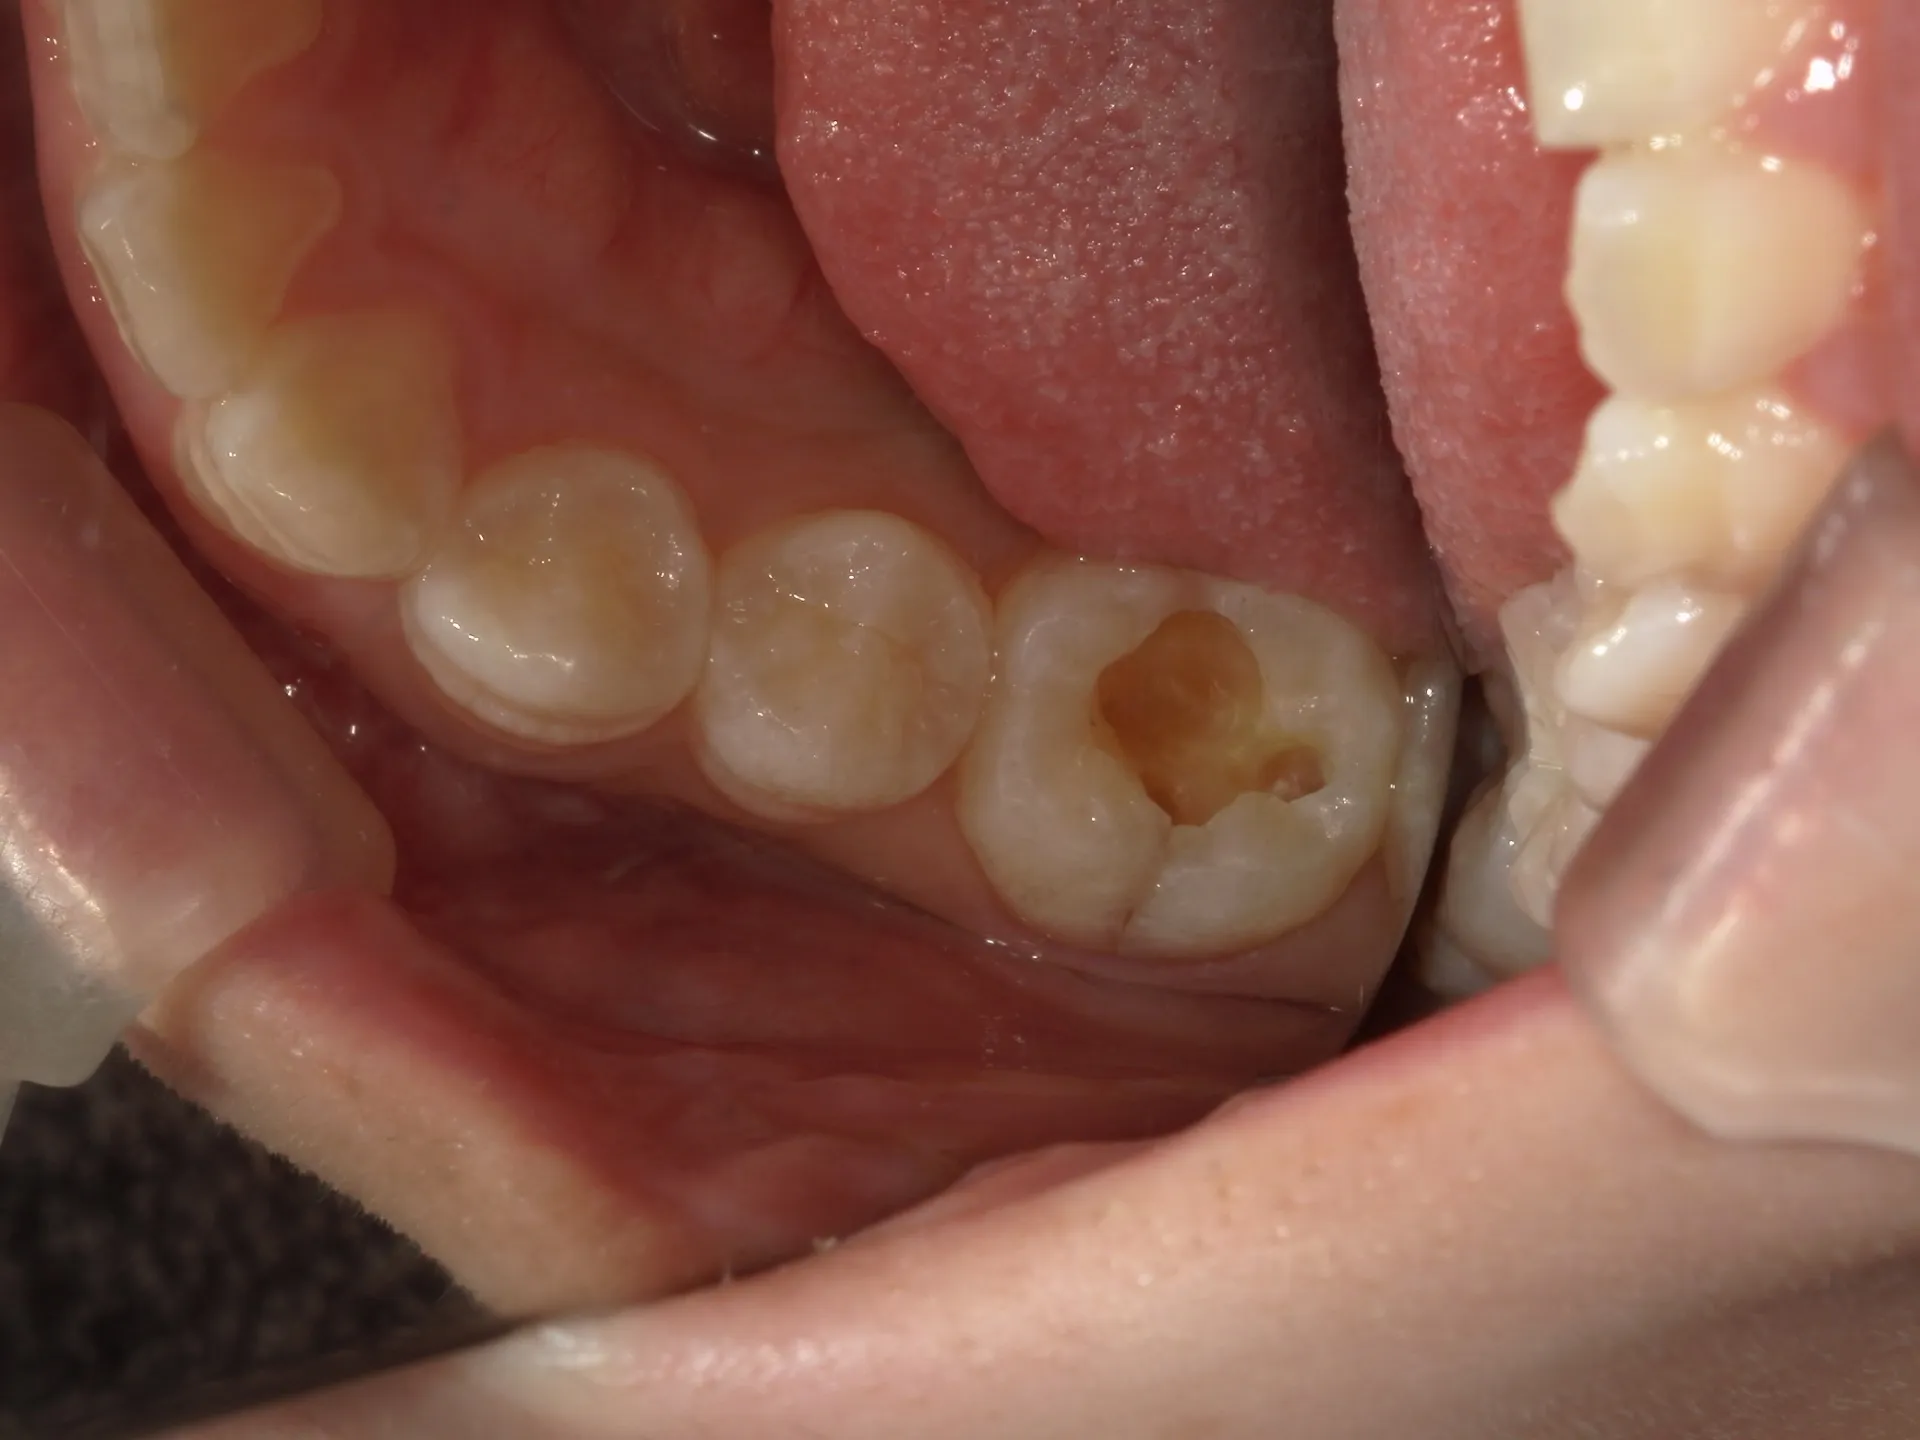

今回は一見問題なく見える歯の詰め物の下に深い虫歯があった治療の症例をご紹介いたします。